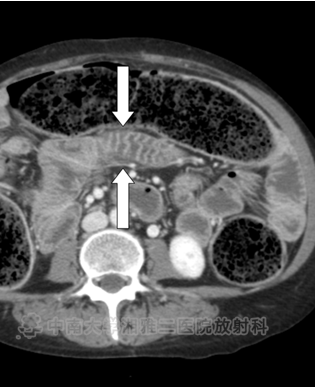

● 对比增强CT显示食管明显扩张(箭头所示)。

● 在结肠中有明显的粪块残留,在结肠壁(箭头)内存在气体,相关肠壁无增厚或肠系膜脂肪的滞留,与结肠囊样积气一致。